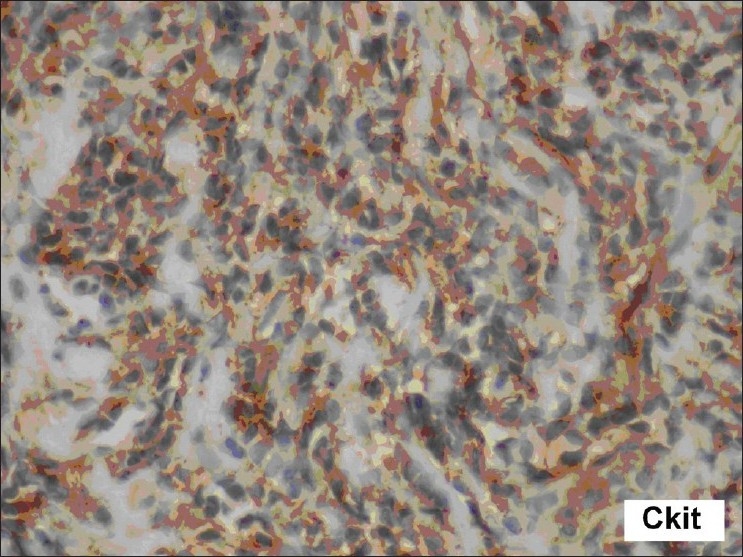

The cervix biopsy [Figure 1] showed a low-grade, endometrial uterine sarcoma, composed of short, spindleshaped cells with round-to-oval nuclei, finely clumped chromatin, inconspicuous nucleoli, and eosinophilic cytoplasm, in the presence of scattered mitotic figures that were present. Immunohistochemistry showed CD117 positivity and CD 10 positivity in the tumor cells [Figure 2]. Urine Bence Jones Protein was negative. Bone marrow biopsy was positive for malignant cells. The Technetium 99 MDP Bone scan revealed multiple bone metastases. She was surgically inoperable; therefore, she was treated with tyrosine kinase inhibitor-Imatinib Mesylate 400 mg, once daily. She had generalized osteoporosis with multiple metastasis, hence, she was given oral Bisphosphonates[4] (Ibandronate 30 mg for 14 days every month) for three months. Palliative local external beam radiotherapy was directed to the secondaries in the Spine from D8 to L12 and the bilateral sacroiliac region, with total dose of 30 Gy in 10 fractions. As she continued to have pain with persistence of vaginal discharge, concurrent palliative chemotherapy with Adriamycin 70 mg and Ifosphamide 5 gm (two cycles) were given, in addition to the oral Imatinib 400 mg once daily. On a subsequent follow-up, the patient had swelling in the left jaw. The repeat bone scan showed increased uptake in the left mandibular region of the jaw, suggestive of metastasis, due to the progressive disease (differentiated from Bisphosphonates-induced osteoradionecrosis, which occurred due to prolonged use of Bisphosphonates or with previous exposure to radiation). After two cycles of Ifosphamide and Adriamycin, the chemotherapy regimen was changed to Paclitaxol 260 mg and Gemcitabine 1000 mg as the disease was progressive. The dose of Imatinib Mesylate was not escalated as the patient did not respond to Imatinib, and it was used either as a single agent or used with combination chemotherapy. Due to financial constraints the genetic tests for exon 9 or other mutations were not done and the next choice of Sunitinib was opted out. Although Imatinib Mesyate and Ibandronate were continued, she had progressive disease within a short duration of time and succumbed to her illness.

| Figure 2 Immunohistochemistry in high power microscopy 40× showed CD117 positivity and CD 10 positivity in the tumor cells